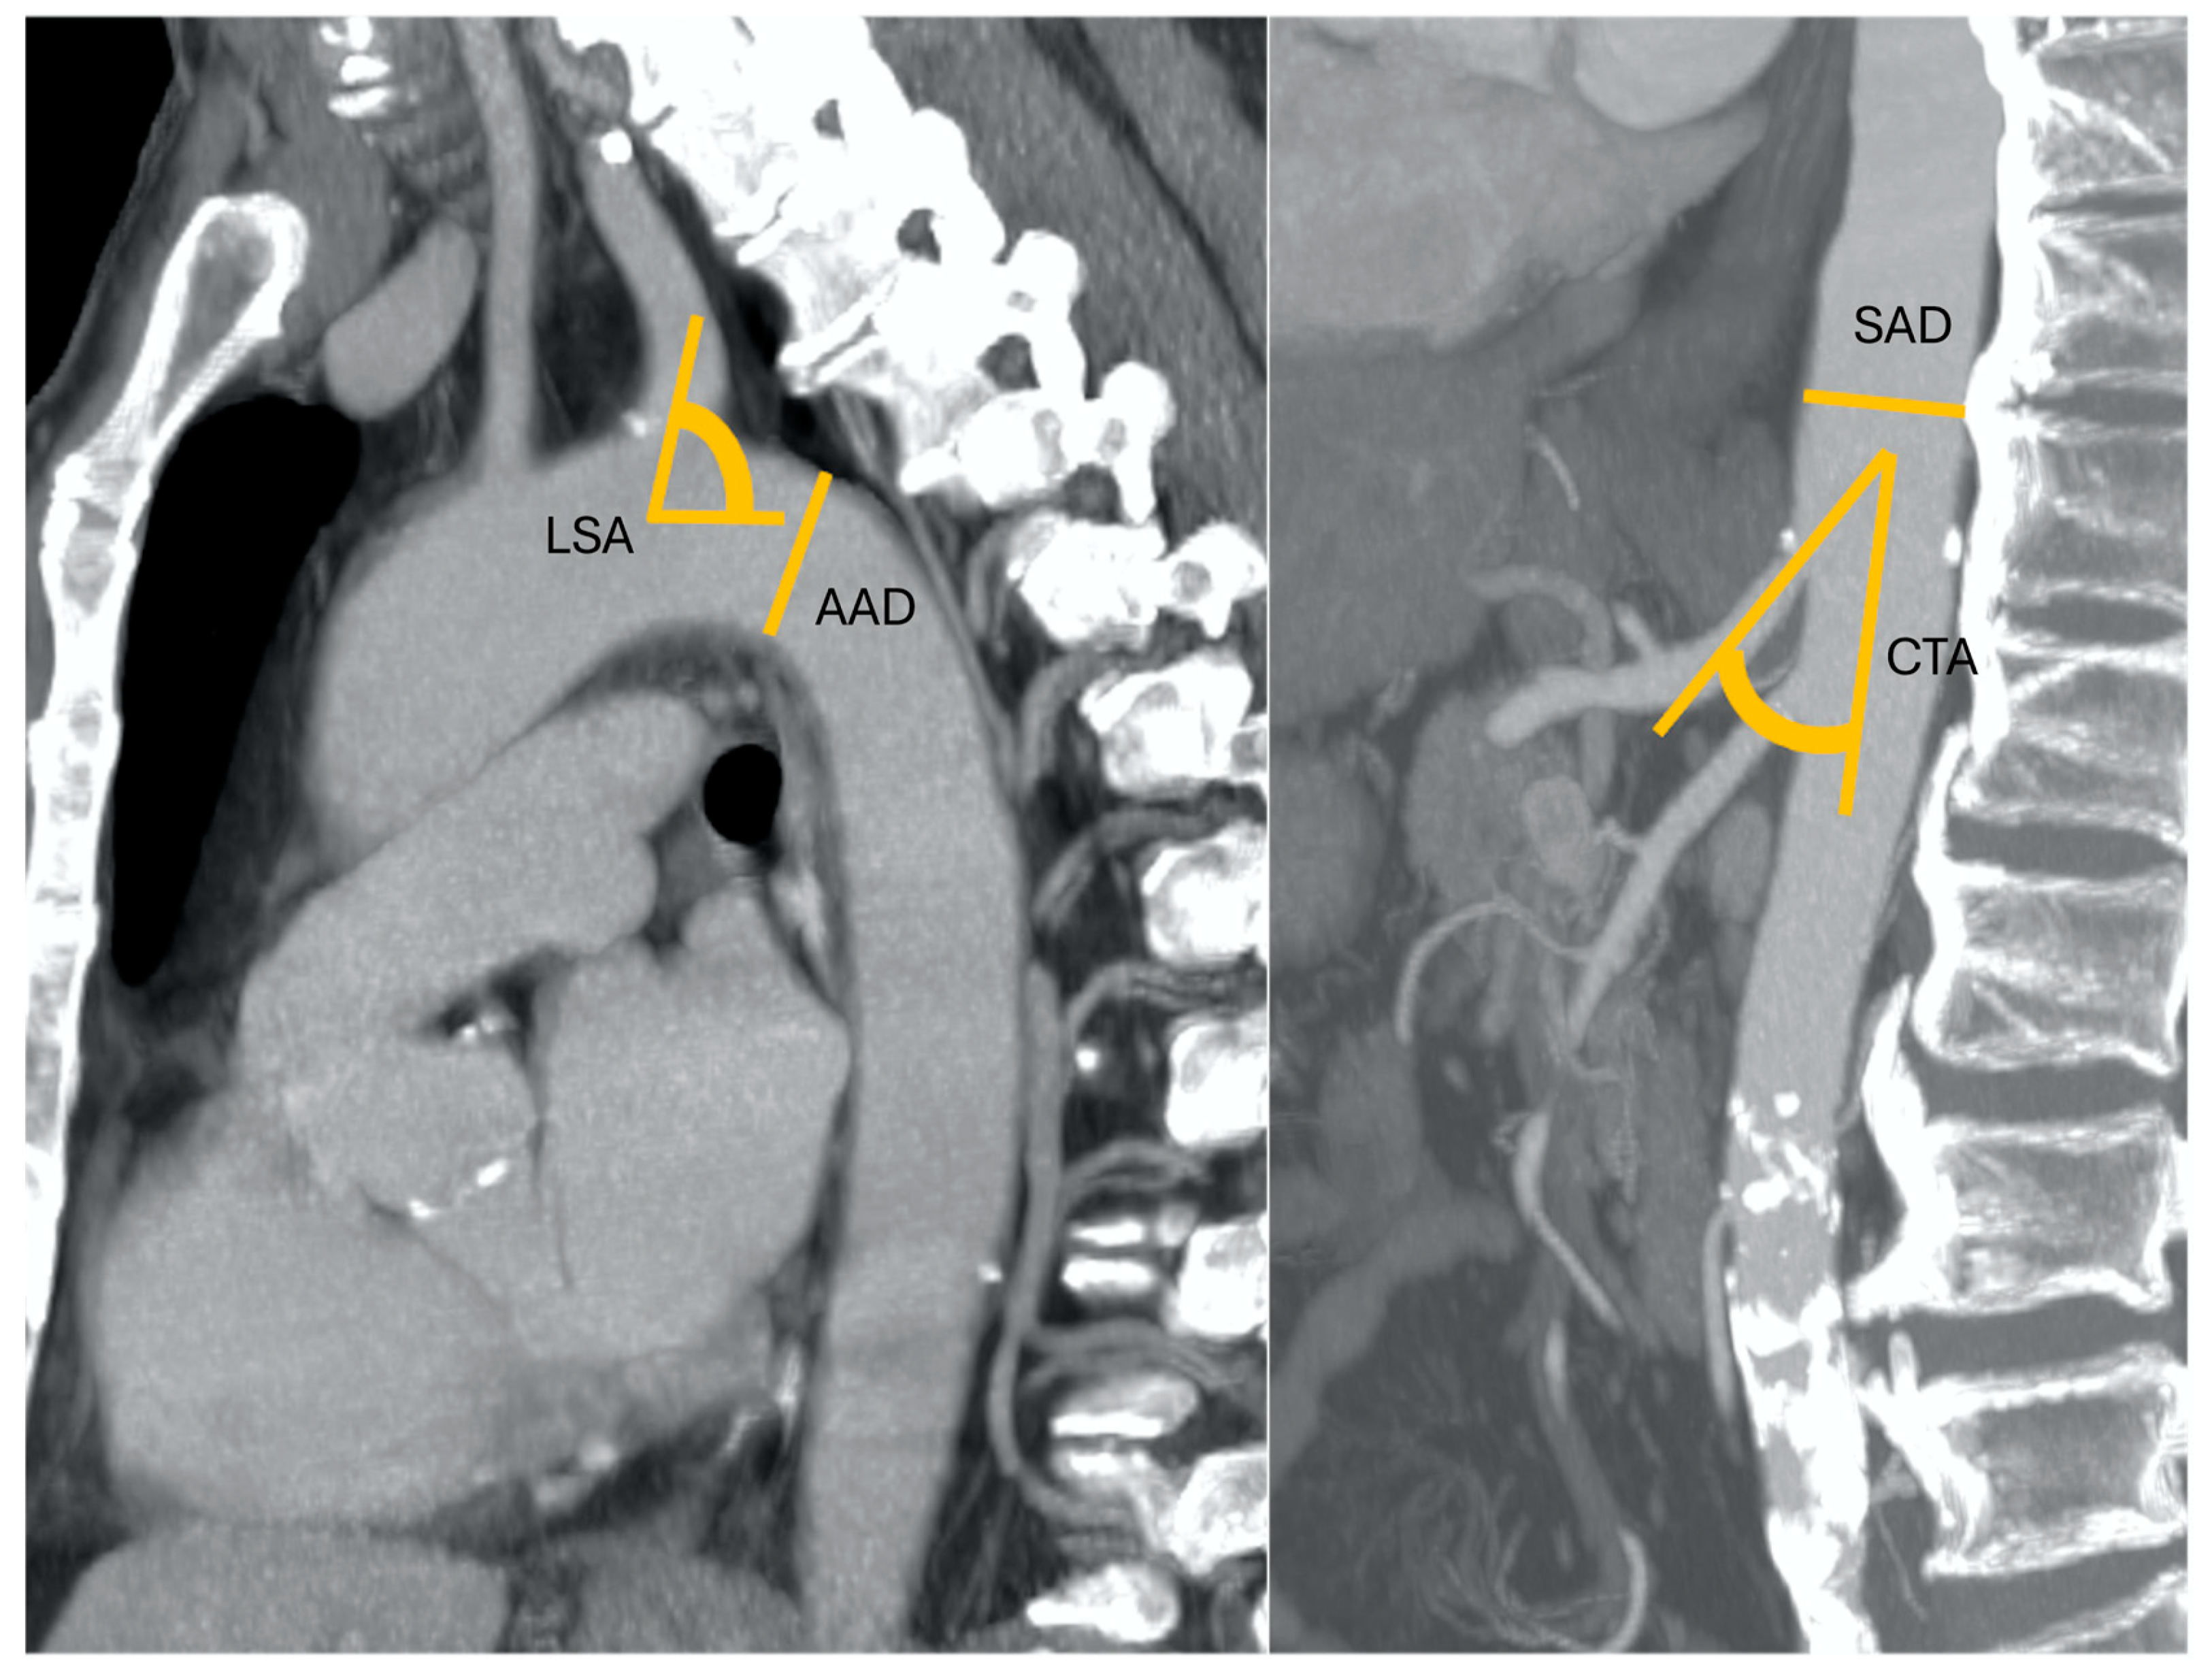

Pre-procedural CT examinations were retrospectively analyzed independently by two radiologists, each one with more than five years of experience in thoraco-abdominal radiology. Readers were blinded to medical history, clinical parameters, and procedural details. The following data were collected for all the CT examinations performed prior to the procedure: aortic arch diameter (AAD, measured at the level of origin of subclavian artery) and angulation (AAA) according to Madhwal and colleagues [8]; left subclavian artery angulation (LSA); descending thoracic aorta diameter evaluated in the proximal tract; angulation of descending thoracic aorta (according to the classification by Belvroy and colleagues [9]; suprarenal abdominal aorta diameter (SAD) measured at the level of origin of celiac trunk; take-off angle of celiac trunk (CTA); anatomical variants of the hepatic artery [10,11]; and previous aortic and periaortic vessel interventions, if any. The data sets of each patient were loaded into a dedicated three-dimensional workstation (Advantage Workstation VolumeShare 4; GE Healthcare, Milwaukee, WI, USA). For length measurements, reformatted cross-sectional images longitudinal to the long axis of the vessel were automatically obtained to create “modified coronal” planes. Vessel segmentation was automatically performed. All measurements of diameters, lengths and angles were manually completed using graphical measurement tools in the post-processing application software. To minimize variability, the two experienced radiologists performed all measurements twice, and the final mean values were considered.

Figure 1. A 52-year-old patient with nodular HCC in the left liver lobe with a radial diameter (RD) of 3 mm (0 points), left subclavian artery angle (LSA) of 85° (0 points), an aortic arch angulation (AAA) type I (0 points) with a diameter (AAD) of 32 mm (1 point), suprarenal aorta diameter (SAD) of 23 mm (0 points), and celiac trunk angle (CTA) of 45° (0 points). Final RAD-access score: 0, transradial access preferred for values between 0 and 2.